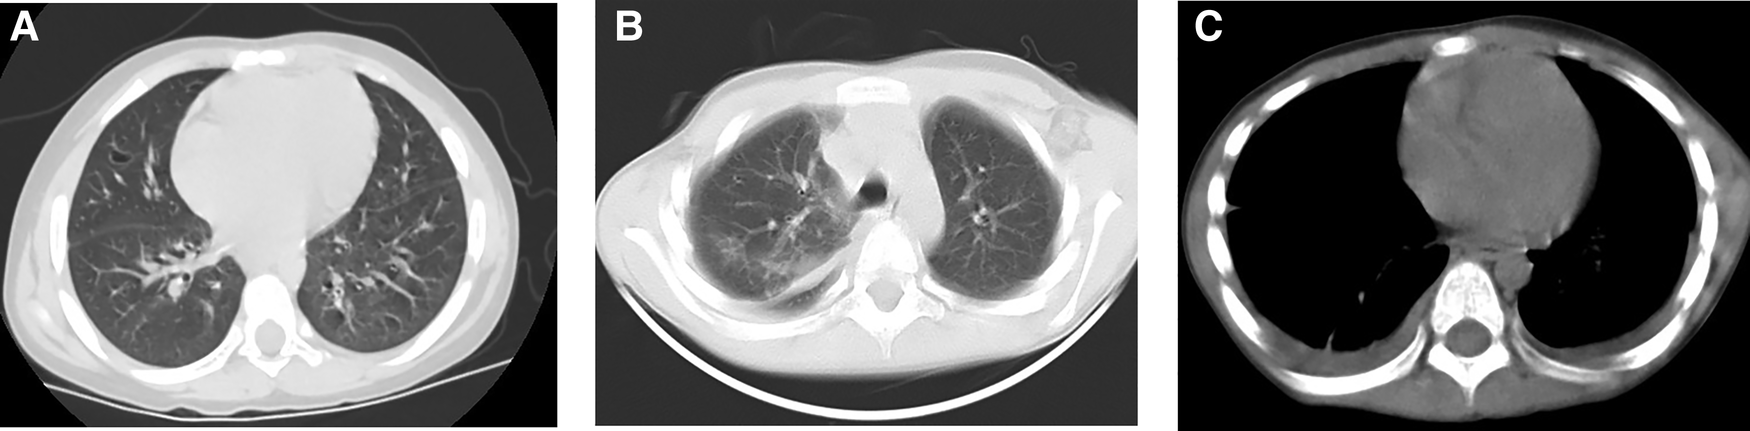

Figure 1

A 5-year-old boy had habit of drinking untreated water. CT of the lungs showed cystic areas (A), pulmonary exudation (B) and pleural effusion (C).

On pulmonary CT, the most common findings were pleural effusion (68.9%) and alveolar exudation (64.4%) (Supplementary Material S3, Figure 1). Brain edema, nodules, and cerebral hemorrhage were found in children with cerebral paragonimiasis (Supplementary Material S3, Figure 2). Pleural effusion was one of the most important findings of ultrasonography. In addition, ultrasound examination also showed abdominal effusion, pericardial effusion, and subcutaneous nodules.